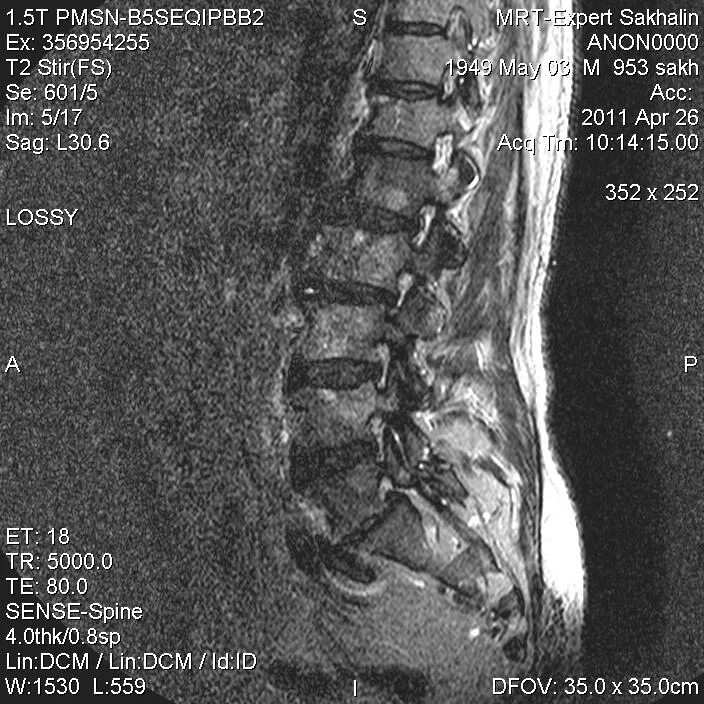

Метастазы в поясничном отделе симптомы